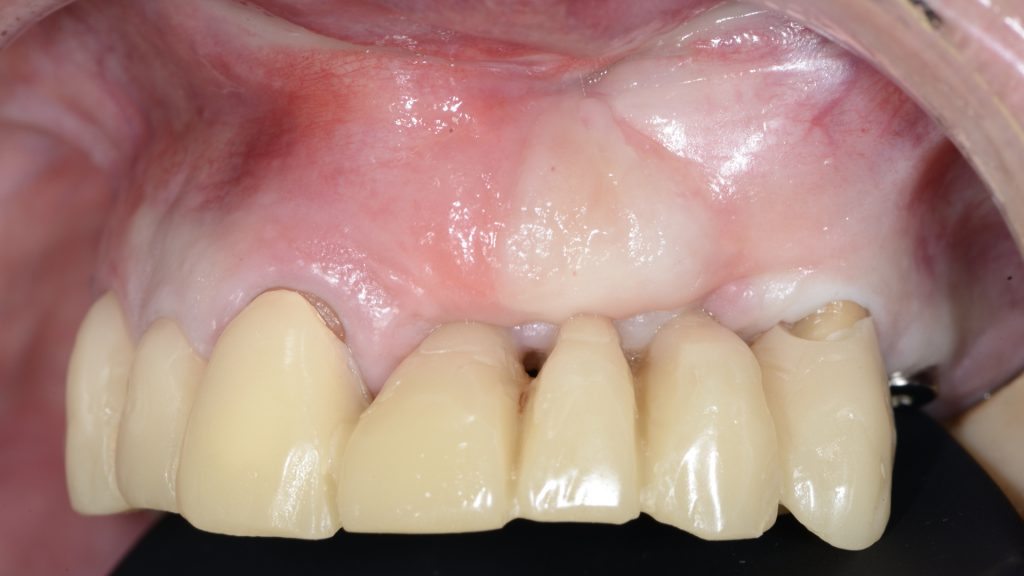

Situación clínica previa al segundo procedimIento quirúrgico. Vista vestibular.

Situación clínica previa al tercer procedimiento quirúrgico. Vista vestibular.